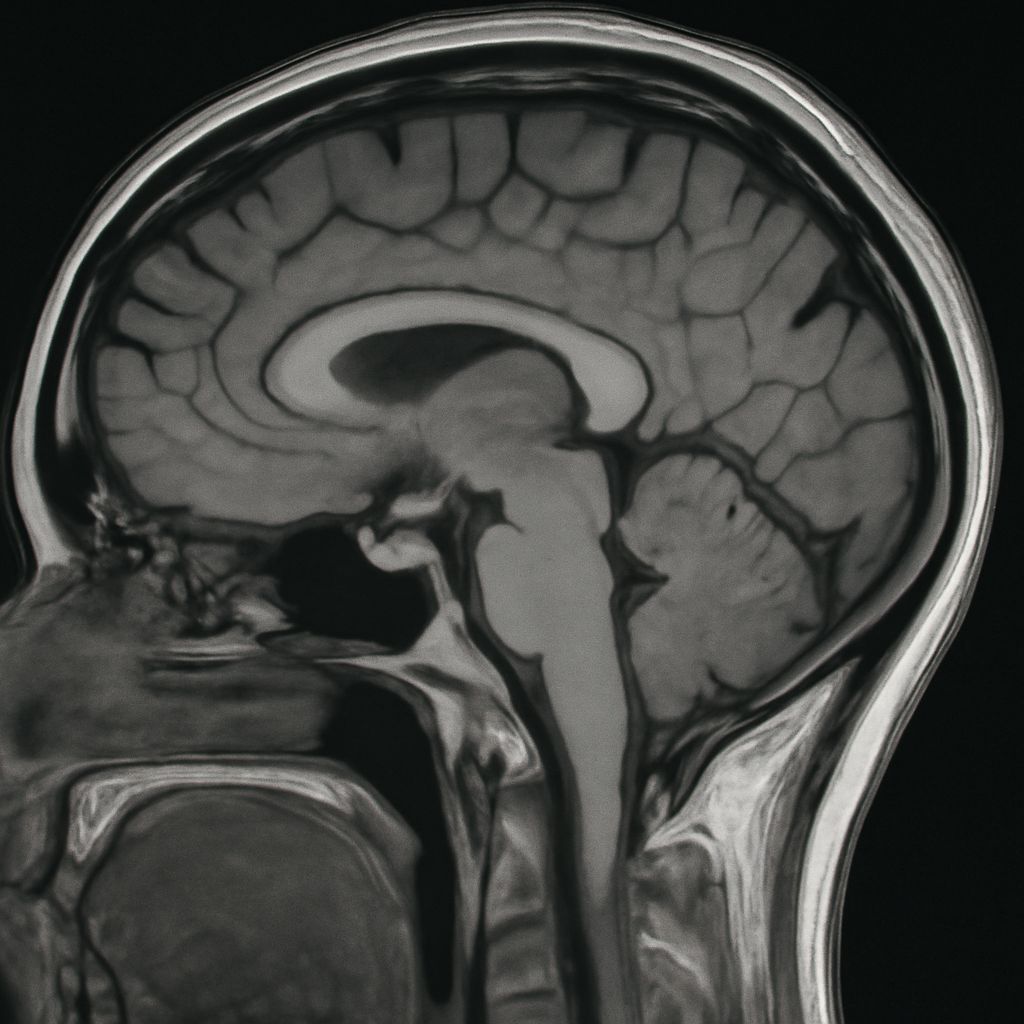

A lumbar spine MRI produces cross-sectional images using magnetic fields and radio waves. The technology is particularly useful for visualizing soft tissue structures that are invisible on standard X-rays. Discs, ligaments, the spinal cord, and nerve roots all appear clearly on MRI images.

Common findings on a lumbar MRI include disc herniation (when disc material bulges or ruptures into the spinal canal), spinal stenosis (narrowing of the canal that can compress nerves), degenerative disc disease, spondylolisthesis (vertebral slipping), and in some cases, tumors or infections. The scan captures these structures in multiple planes, giving the radiologist a complete three-dimensional picture.